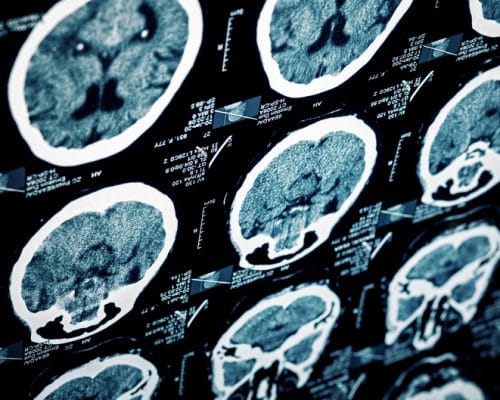

Concussions are a fairly common form of brain injuries that are considered to be minor. They result from an impact to the head or a sudden change in the head’s movement. They typically cannot be seen on an imaging test, like a MRI or a CAT scan, but they can take years to heal. Concussions are particularly dangerous if more than one is sustained, such as often the case with professional athletes.

In contrast, contusions are more serious types of brain injuries that can be seen on imaging. They are bruises on the brain that result from a direct impact to the head. Large contusions are treated through surgery.